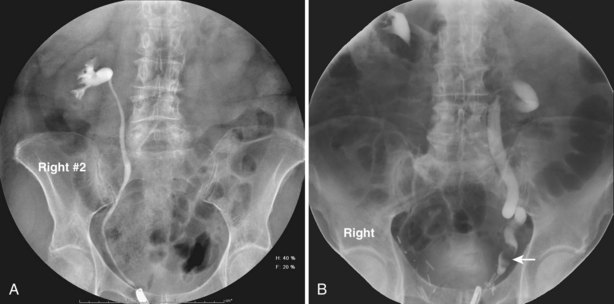

The other commonly employed method is the use of an obstructing ureteral catheter such as a bulb-tip, cone-tip, or wedge-tip catheter. These catheters are inserted into the ureteral orifice and then pulled back against the orifice to effectively obstruct the ureter. Contrast is then injected to opacify the ureter and intrarenal collecting system. Depending on the indication for the study, it is useful to dilute the contrast material to 50% or less with sterile fluid. This prevents subtle filling defects in the collecting system or ureter from being obscured. Contrast is injected slowly, usually requiring from 5 to 8 mL to completely opacify the ureter and intrarenal collecting system in adults (Fig. 4–6). More or less contrast may be required depending on the size of the patient and the capaciousness of the collecting system. Limited use of fluoroscopy while injecting will help prevent overdistension of the collecting system and reduce the risk of extravasation of contrast. Care should be taken to evacuate air bubbles from the syringe and catheter before injection. Such air bubble artifacts could be mistaken for stones or tumors.

Figure 4–6 A, Right retrograde pyelogram performed using an 8-Fr cone-tipped ureteral catheter and dilute contrast material. The ureter and intrarenal collecting system are normal. B, Left retrograde pyelogram using an 8-Fr cone-tipped ureteral catheter. A filling defect in the left distal ureter (arrow) is a low-grade transitional cell carcinoma. The ureter demonstrates dilation, elongation, and tortuosity, the hallmarks of chronic obstruction.